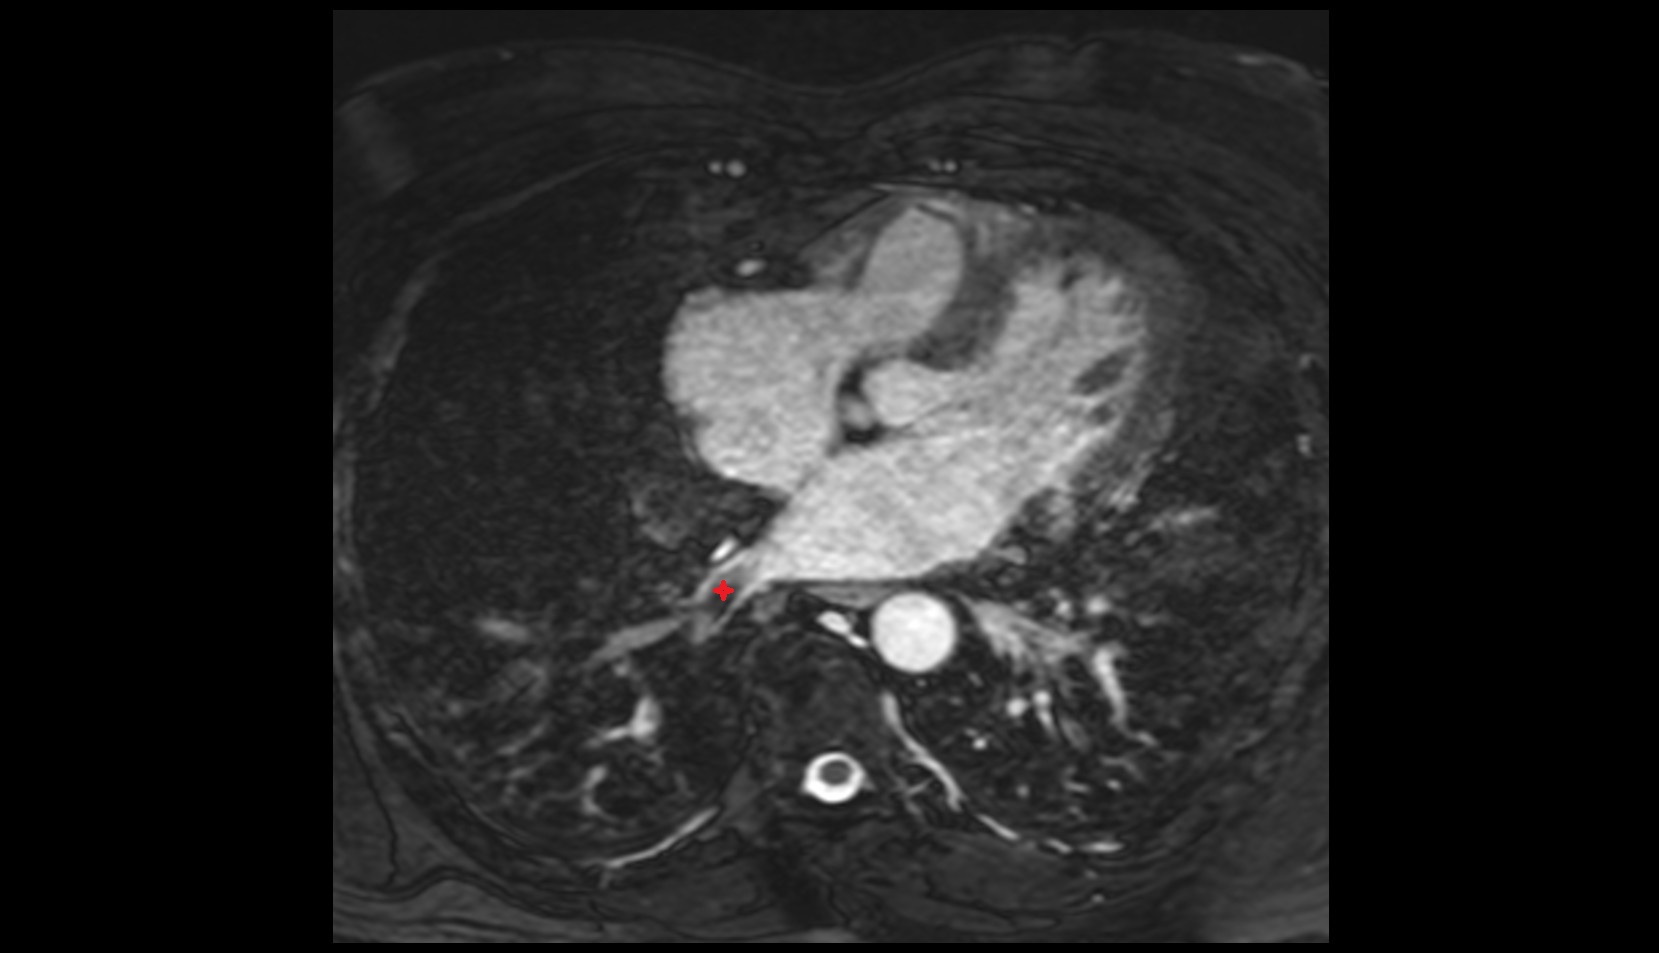

- Heart

- Left ventricle

- Right atrium

- Left atrium

- Right ventricle